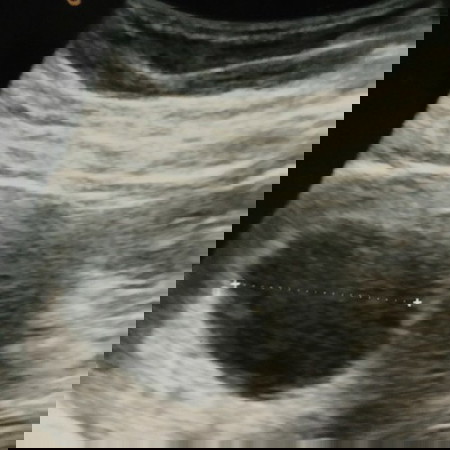

hamil 7w3d

bunda tadi siang saya usg kata dokter sudah 7w3d tapi embrionya belum kelihatan alias BO katanya.. cuma kantong aja.. apa bunda ada yg alamin kayak saya